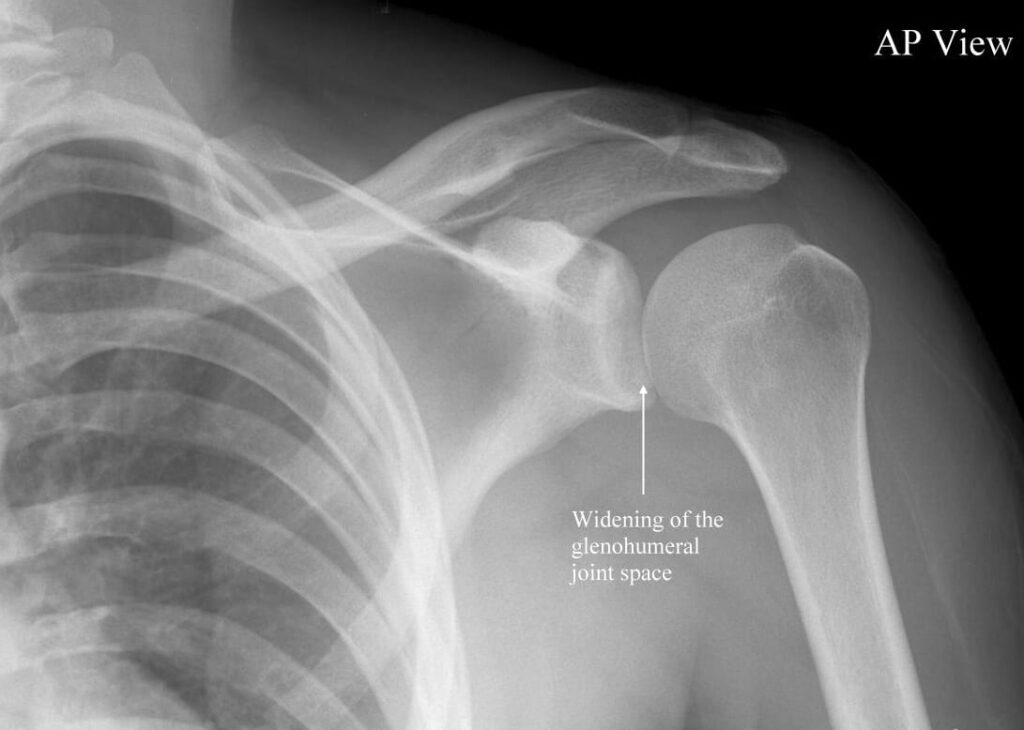

A shoulder dislocation occurs when the upper arm bone pops out of the shoulder socket, leading to pain and joint instability. The most mobile joint in the body is also the most unstable, which is the shoulder. In sports, particularly sports with overhead movement or contact, that mobility is frequently pushed past its normal limits.